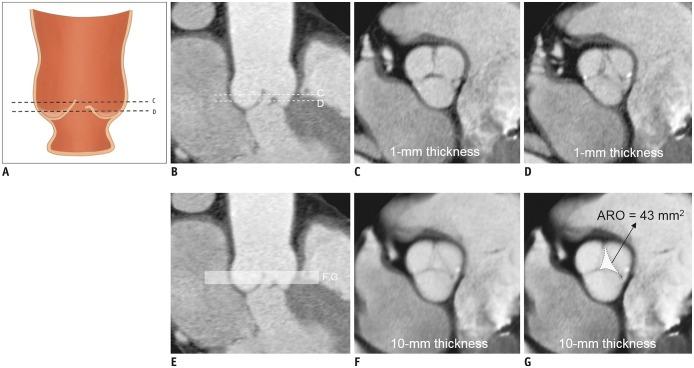

A total of 117 patients (age, 49.4 ± 15.6 years; 83 males) who underwent the David operation for AR were included in this retrospective study. Aortic root profiles including the aortic regurgitant orifice area (ARO) and the aortic cusp asymmetry ratio of the areas (ASR), which is defined as the maximum/minimum areas among the three cusp areas at the level of the commissures, were measured on preoperative cardiac CT scans. Clinical and CT findings were compared between a group with recurrent AR grade < 3 (no, trivial, or mild AR) and recurrent ≥ 3 + AR. To determine the optimal cut-off values of ASR and ARO, the receiver operating characteristic (ROC) curve was used. Cox regression analysis was used for the analysis of the factors affecting recurrent 3 + AR.

Postoperatively, recurrent 3 + AR developed in 17 (14.5%) patients and occurred within a median of 268 days (interquartile range: 78-582 days). The cut-off ARO value for discriminating the patients with recurrent 3 + AR was > 24 mm² (sensitivity, 76.5%; specificity 64.8%), and the area under the ROC curve (AUC) was 0.72. For ASR, the cut-off value was > 1.58 (sensitivity, 76.5%; specificity, 58.0%) and the AUC was 0.64. Multivariable Cox regression showed that ARO > 24 mm² (hazard ratio = 3.79, = 0.020) was a potential independent parameter for recurrent 3 + AR. ROC for the linear regression model showed that the AUC for both ARO and ASR was 0.73 (95% confidence interval, 0.64-0.81, < 0.001).